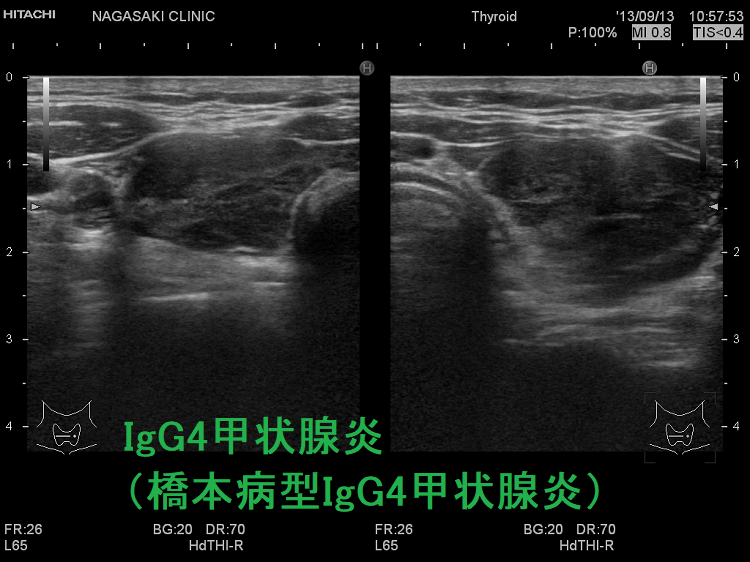

IgG4甲状腺炎(橋本病型IgG4甲状腺炎) 超音波(エコー)画像

橋本病の4.3%でIgG4高値(高ガンマグロブリン血症患者で多い)。IgG4甲状腺炎(橋本病型IgG4甲状腺炎)は急速進行型橋本病で甲状腺機能低下が速く①男性の比率が高い②抗甲状腺ペルオキシダーゼ抗体(TPO抗体)と抗サイログロブリン抗体(Tg抗体)価が高い③超音波エコー画像は巨大甲状腺腫、びまん性低エコー、肉芽腫性炎症による腫瘤形成、エラストグラフィーで硬い。IgG4関連疾患(IgG4-RD)の合併が少ない臓器特異的IgG4関連疾患。通常の橋本病と穿刺細胞診では鑑別不能、組織診(コア生検)で著明な線維化とIgG4免疫染色でIgG4産生形質細胞を確認。

- 超音波(エコー)画像では、巨大な甲状腺腫、内部びまん性低エコー、肉芽腫性炎症による腫瘤形成を認める